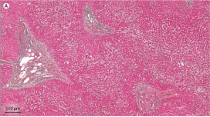

Rubrica iconografica

Una storia a chiazze: la vitiligine

Mazzola S, Zerjal K, Calligaris L, Berti I.

Una patologia cutanea cronica, a volte invalidante, che riguarda anche letà pediatrica (incidenza 1-2% nella popolazione generale). Si riportano le diverse forme, con unimportante novità dei JAK inibitori topici per alcune localizzazioni, dai 12 anni di età.